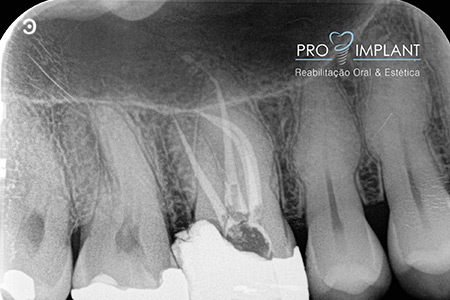

FOTOS

Endodontia